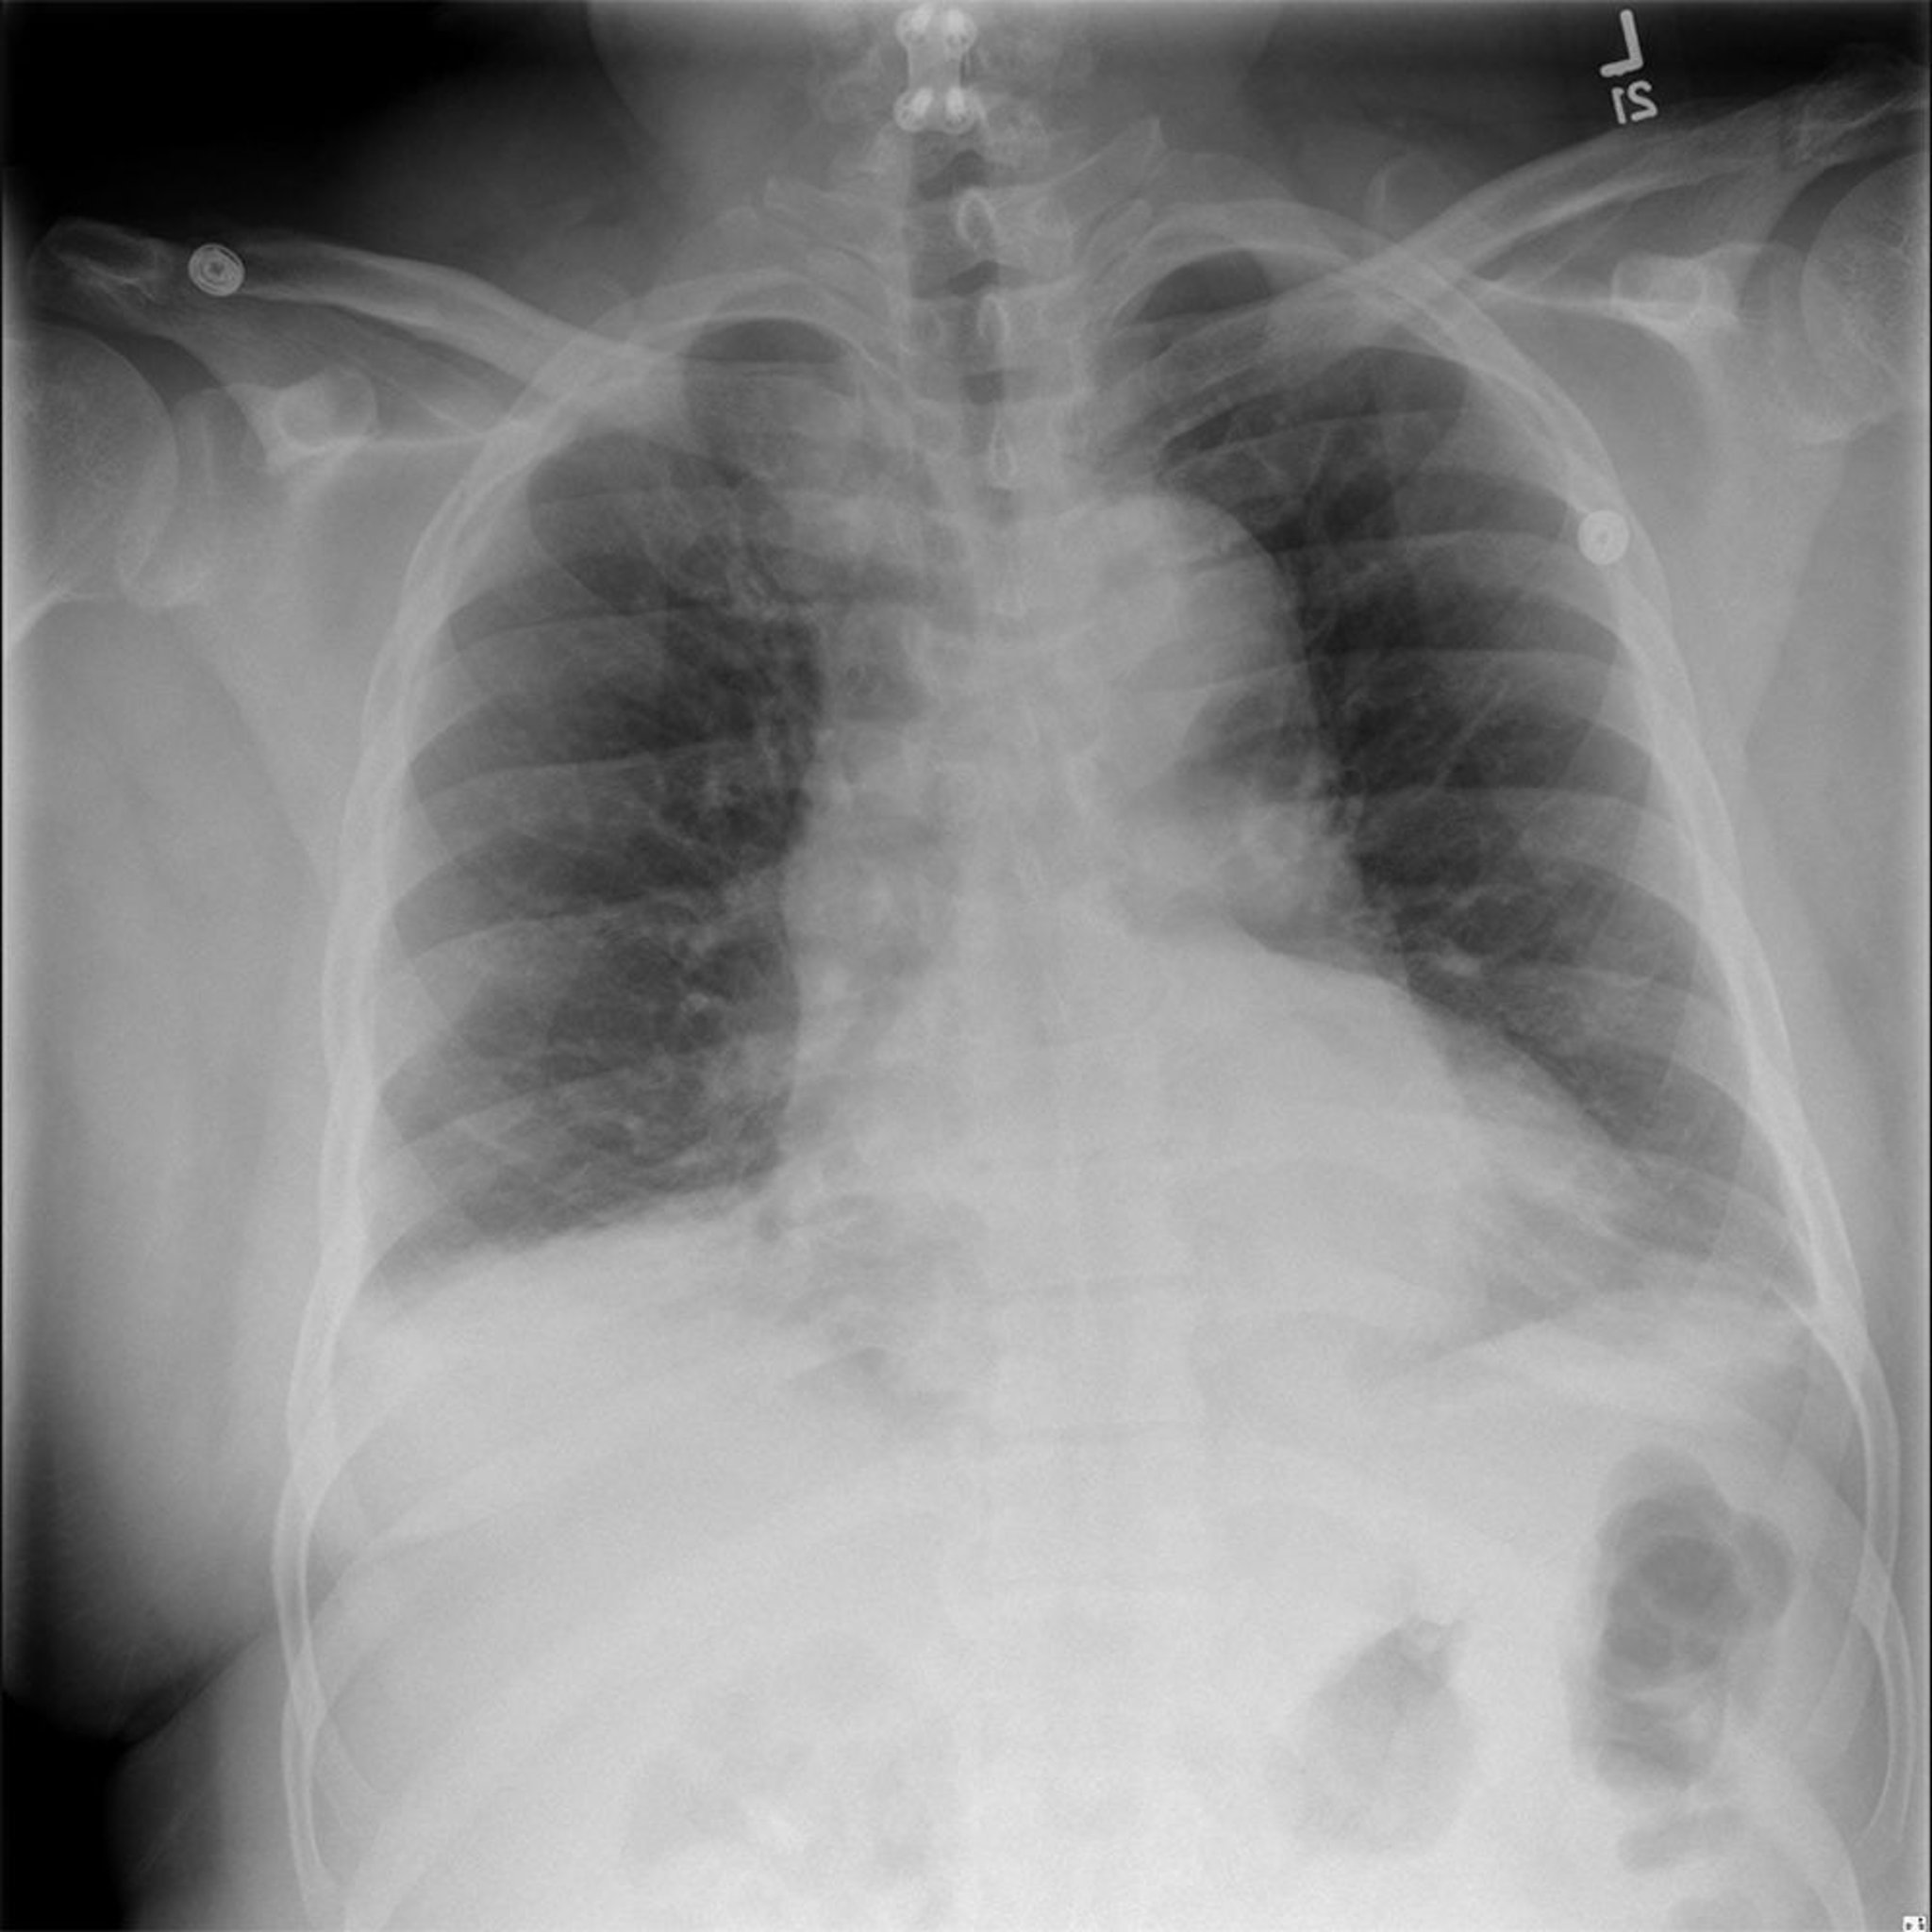

Questa radiografia mostra uno slargamento del mediastino in un paziente con noto aneurisma dell'aorta toracica.